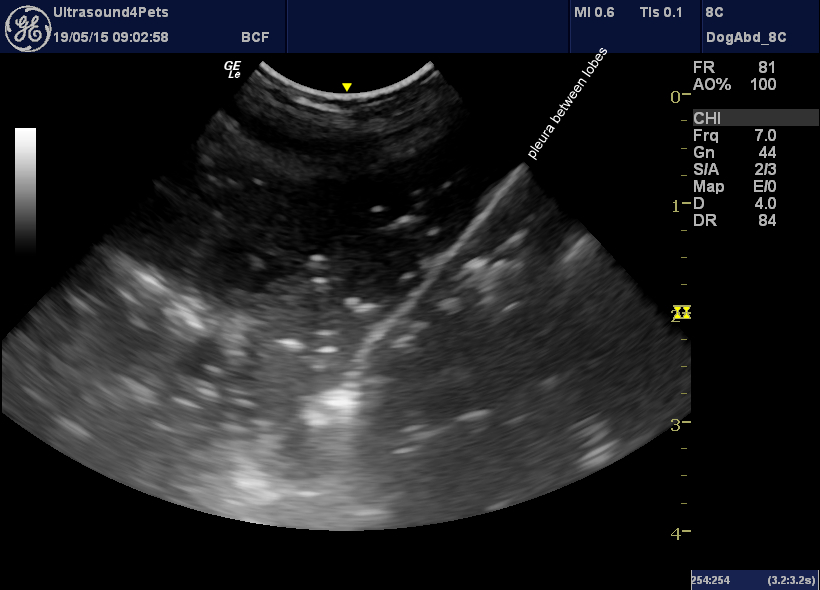

Ultrasonography of pneumothorax

Ultrasonography is surprisingly good as a rapid, readily available imaging modality for screening potential pneumothorax patients. Since cardiogenic pulmonary oedema, pulmonary thromboemboli, pneumonia, pleural effusions and intrathoracic neoplasia can also be detected it’s a powerful tool. The technique can be mastered by anyone with a few minutes to spare. Apply a micro-convex probe to the … Continue reading